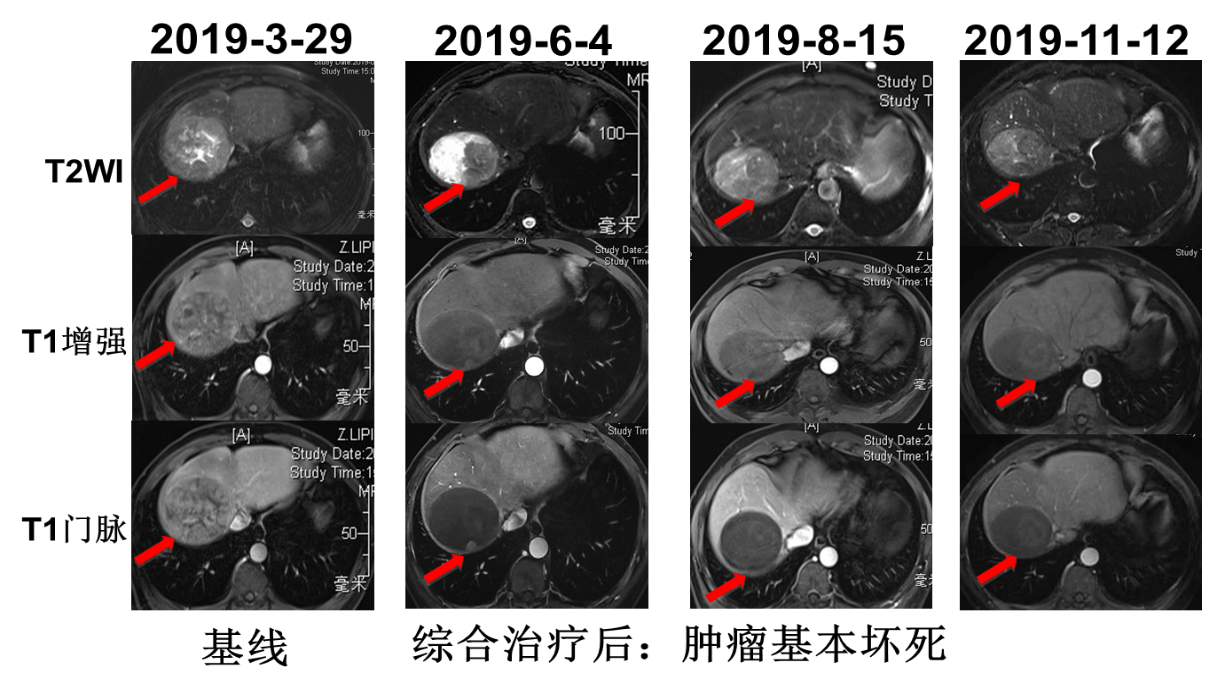

上腹部增强MRI:肝右叶肿瘤,大小约9.6cm×9.5cm,肝右静脉受侵,下腔静脉瘤栓可能,肝囊肿,见图1;肝脏弹性成像超声示:肝右叶弹性硬度测值平均为11.8kPa,考虑肝硬化。

image001.png

图1. 入院后MRI检查

2019年4月2日行TACE+肝肿瘤微波消融术,5月6日起予以信迪利单抗治疗(200mg q3w ivgtt)联合仑伐替尼(12mg qd po),5月10日复查AFP降为正常(10.3ng/ml),PIVKA-Ⅱ降至3352 mAU/ml。6月4日复查肝脏MRI:mPR,局部强化结节,下腔静脉癌栓较前有所好转。7月2日再次行TACE术。术后于7月8日~9月16日行信迪利单抗注射4周期。8月15日复查MRI:mPR,强化结节好转,下腔静脉癌栓有所好转。8月19日复查PIVKA-Ⅱ进一步降至1202mAU/ml。11月12日复查AFP 12.4ng/ml,PIVKA-Ⅱ 1784mAU/ml,MRI提示病灶稳定。治疗经过见图2。MRI疗效评估见图3、图4、图5。

图3. MRI疗效评估

患者为中老年男性,既往有乙型病毒性肝炎病史及抽烟史。2019年3月MRI检查发现右肝占位。肿瘤标志物检测结果AFP为418.8ng/mL;PIVKA-Ⅱ:40208mAU/ml,结合患者病史及影像学检查诊断为肝细胞癌。肿瘤的分期对于预后以及治疗方案的制定具有重要的指导作用,肝细胞癌的分期标准比较多,常用的有巴塞罗那(BCLC)分期和TNM分期,本例患者根据巴塞罗那分期定为C期;TNM分期为T4N0M0,IIIB期。患者的体能状态评价根据ECOG标准评分为0分;肝功能化验无明显异常,Child-Pugh 评级为A级。总体来说,患者肝脏病灶局限,无远处转移,并且体能状态以及肝功能良好,于2019年4月2日针对肝脏病灶行TACE+肝肿瘤微波消融术,术后1个月起(5月6日)信迪利单抗联合仑伐替尼治疗,5月10日复查肿瘤标志物明显降低。6月4日复查发现原病灶周边强化结节,于是再次行TACE治疗,术后继续给以信迪利单抗联合仑伐替尼治疗。2019年8月15日复查,MRI显示原病灶强化结节及下腔静脉癌栓有所好转。至11月12日,信迪利单抗治疗已10个周期,复查肿瘤标志物及MRI均提示病灶稳定。